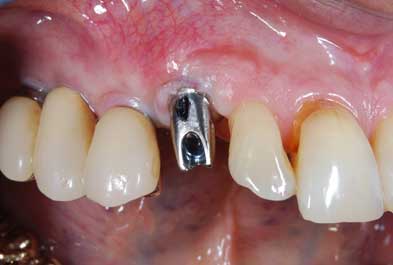

IMPIANTI POST-ESTRATTIVI

Impianto post-estrattivo

In un paziente cardiopatico di 72 anni